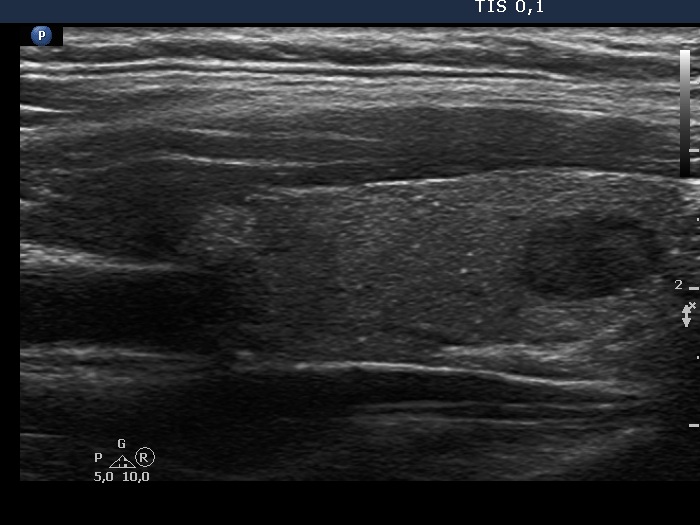

Left lobe, another longitudinal scan. The isolated microcalcifications far from the tumor focus are signs of invasive spread.